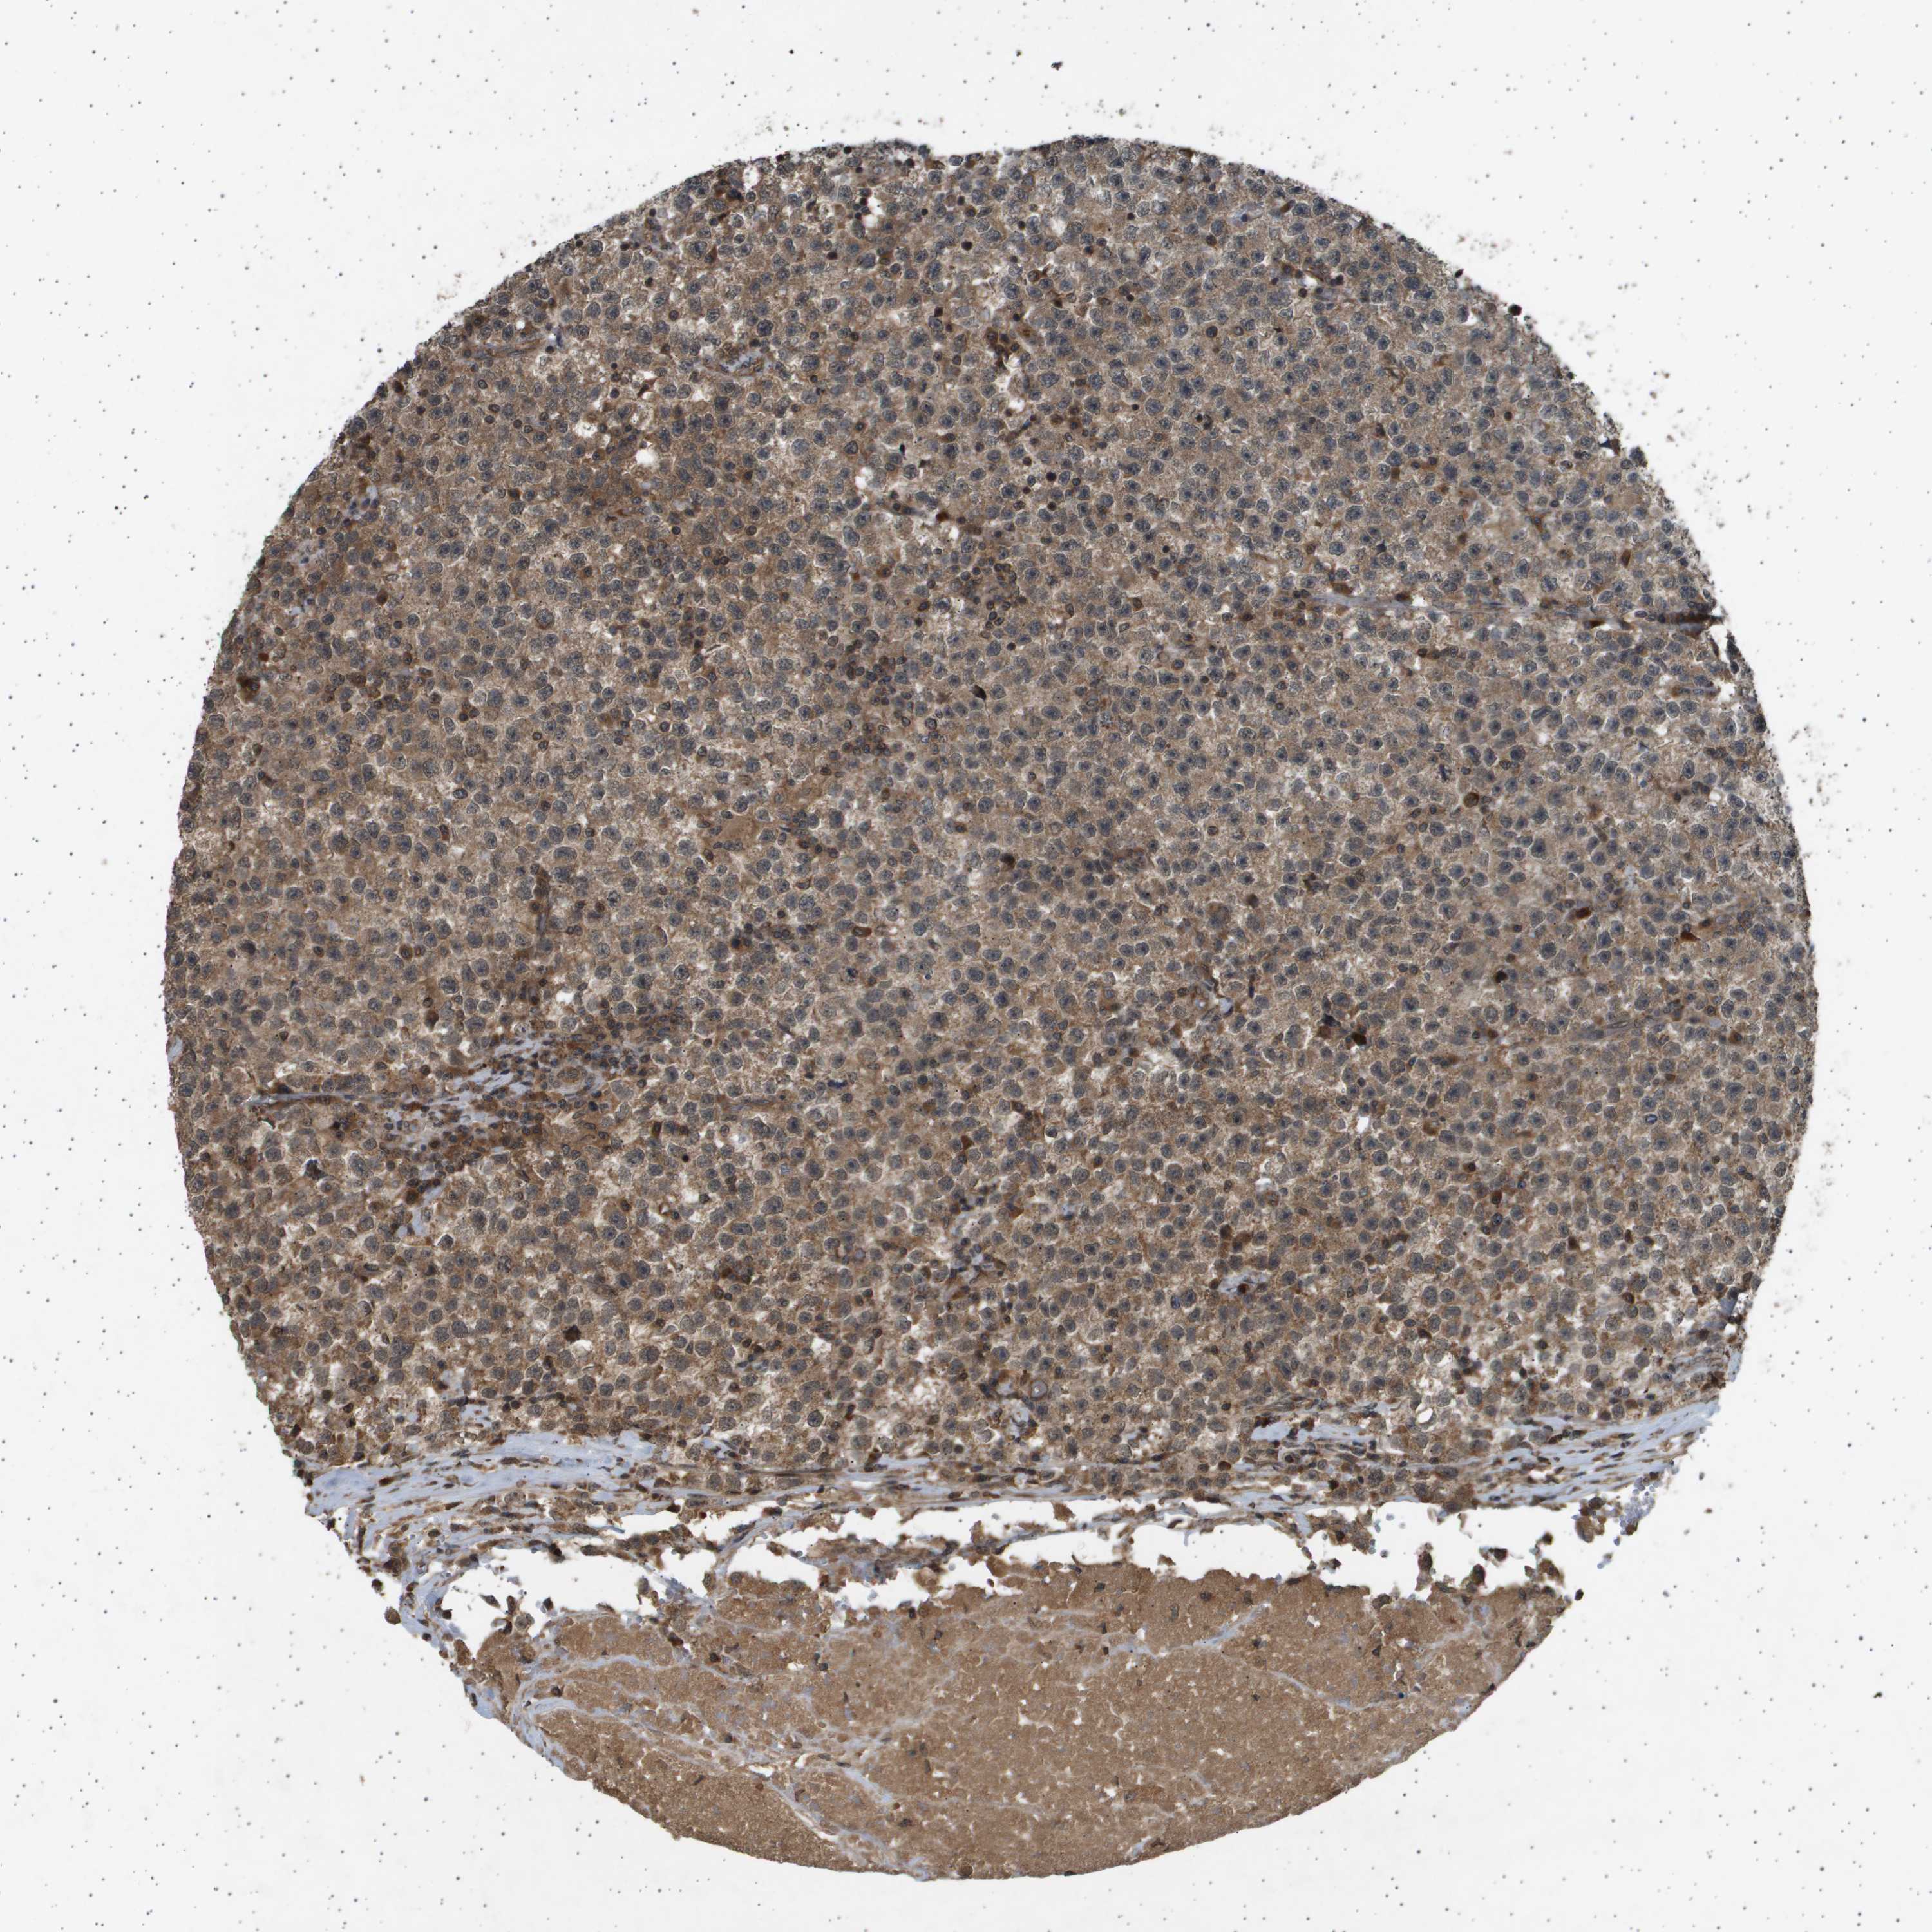

TESTIS CANCER - Protein expressioni

A mouse-over function shows sample information and annotation data. Click on an image to view it in a full screen mode. Samples can be filtered based on level of antibody staining by selecting one or several of the following categories: high, medium, low and not detected. The assay and annotation is described here.

Note that samples used for immunohistochemistry by the Human Protein Atlas do not correspond to samples in the TCGA dataset.

Antibody stainingi

Antibody staining in the annotated cell types in the current human tissue is reported as not detected, low, medium, or high, based on conventional immunohistochemistry profiling in selected tissues. This score is based on the combination of the staining intensity and fraction of stained cells.

Each image is clickable and will lead to virtual microscopy that enables deeper exploration of all samples and also displays staining intensity scores, fraction scores and subcellular localization as well as patient and tissue information for each sample.

Antibody HPA017869

Staining

High

Medium

Low

Not detected

Intensity

Strong

Moderate

Weak

Negative

Quantity

>75%

75%-25%

<25%

None

Location

Nuclear

Cytoplasmic/membranous

Cytoplasmic/membranous,nuclear

Carcinoma, Embryonal, NOS

Seminoma, NOS